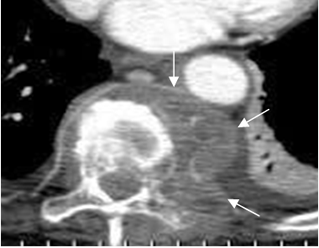

Fig 146. Absceso TBC.

TAC axial. Gran colección paraespinal izquierda, que desplaza la aorta y ensancha el mediastino, por absceso TBC.